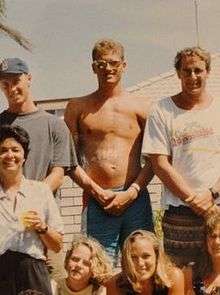

Male showing left pectoral absent

Male showing left pectoral absent - Brachydactyly (Short fingers)